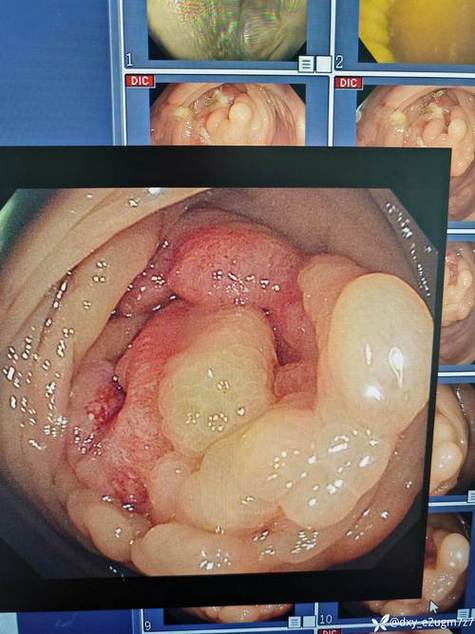

• 大肠癌

大肠癌是指大肠粘膜上皮在环境或遗传等多种致癌因素作用下发生的恶性病变。其预后不良,死亡率较高,是我国常见的恶性肿瘤之一。起源于间叶组织者称为肉瘤,约占大肠恶性病变的1%   1、环境因素   经研究证明,在各种环境因素中,以饮食因素最重要。大肠癌的发病率与食物中的高脂肪消耗量有正相关系。另外,也可能与微量元素缺乏、生活习惯改变有关   早期大肠癌症状不明显。随着癌肿进展,症状逐渐明显,表现为大便习惯改变、便血、腹痛、腹块、发热、贫血和消瘦等全身毒性症状。因肿瘤浸润转移可引起相应器官的改变。大肠癌依其原发部位不同而呈现不同的临床征象和体征   一、实验室检查  ...